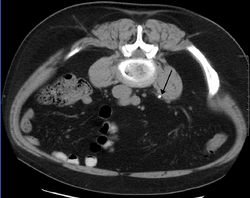

Otherwise a noncontrast helical CT scan with 5 millimeters (0.2 in) sections is the diagnostic method to use to detect kidney stones and confirm the diagnosis of kidney stone disease.[13][47][51][52][7] Near all stones are detectable on CT scans with the exception of those composed of certain drug residues in the urine,[53] such as from indinavir. Calcium-containing stones are relatively radiodense, and they can often be detected by a traditional radiograph of the abdomen that includes the kidneys, ureters, and bladder (KUB film).[53] Some 60% of all renal stones are radiopaque.[51][54] In general, calcium phosphate stones have the greatest density, followed by calcium oxalate and magnesium ammonium phosphate stones. Cystine calculi are only faintly radiodense, while uric acid stones are usually entirely radiolucent.[55]

Measurement of a 5.6 mm large kidney stone in soft tissue versus skeletal CT window.

Bilateral staghorn calculi as seen on CT